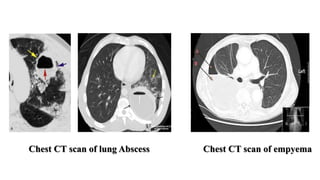

Chest CT scan of lung Abscess Chest CT scan of empyema

Differential diagnostic featuresbetween abscess and empyema in CT: • Relationship to adjacent bronchi/vessels • abscesses doesn’t interrupt the Broncho vascular structures • empyema will usually distort and compress adjacent lung • Shape • Round/spherical in abscess • Elliptical in empyema • split pleura sign • Wall • abscesses have thick irregular walls • empyema are usually smoother • Angle with chest wall • abscesses usually have an acute angle • empyema tends to have obtuse angles

Chest CT scanof lung Abscess Chest CT scan of empyema